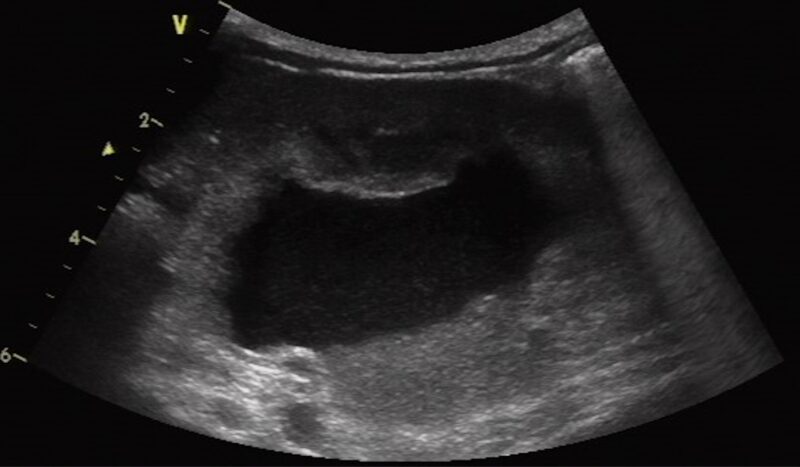

Die Sonographie ist die Methode der Wahl, um CKD-typische Veränderungen (kleinere, unregelmäßige, oft hyperechogene Nieren) zu erkennen, postrenale Ursachen (Pyelektasie, Harnleiterdilatation, Harnblasensteine) auszuschließen und Begleitbefunde zu dokumentieren. Röntgen kann ergänzend eingesetzt werden, z. B. wenn Mineralisationen oder Nephrolithen vermutet werden.